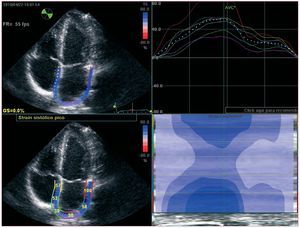

La función diastólica y su valoración mantienen su participación en el índice de publicaciones; el estudio de la función auricular izquierda con las nuevas tecnologías ha sido ampliamente investigado y debatido (fig. 3); el artículo de revisión de la Clínica Mayo compendia el conocimiento actual del tema40. El Hospital Gregorio Marañón publica un ambicioso trabajo experimental y clínico para la valoración de la relajación a través de gradientes de presión intracavitaria telesistólicos medidos por Doppler41.

Figura 3. Strain longitudinal de las paredes de la aurícula izquierda durante la sístole ventricular en un paciente normal. Como es lógico, la aurícula se expande en sístole y las paredes se distienden y crean un strain positivo. Puede observarse que el strain de los segmentos más cercanos al anillo auriculoventricular es mayor que los segmentos medios, y estos, a su vez, son mayores que los segmentos más posteriores, que corresponden al techo de la aurícula.